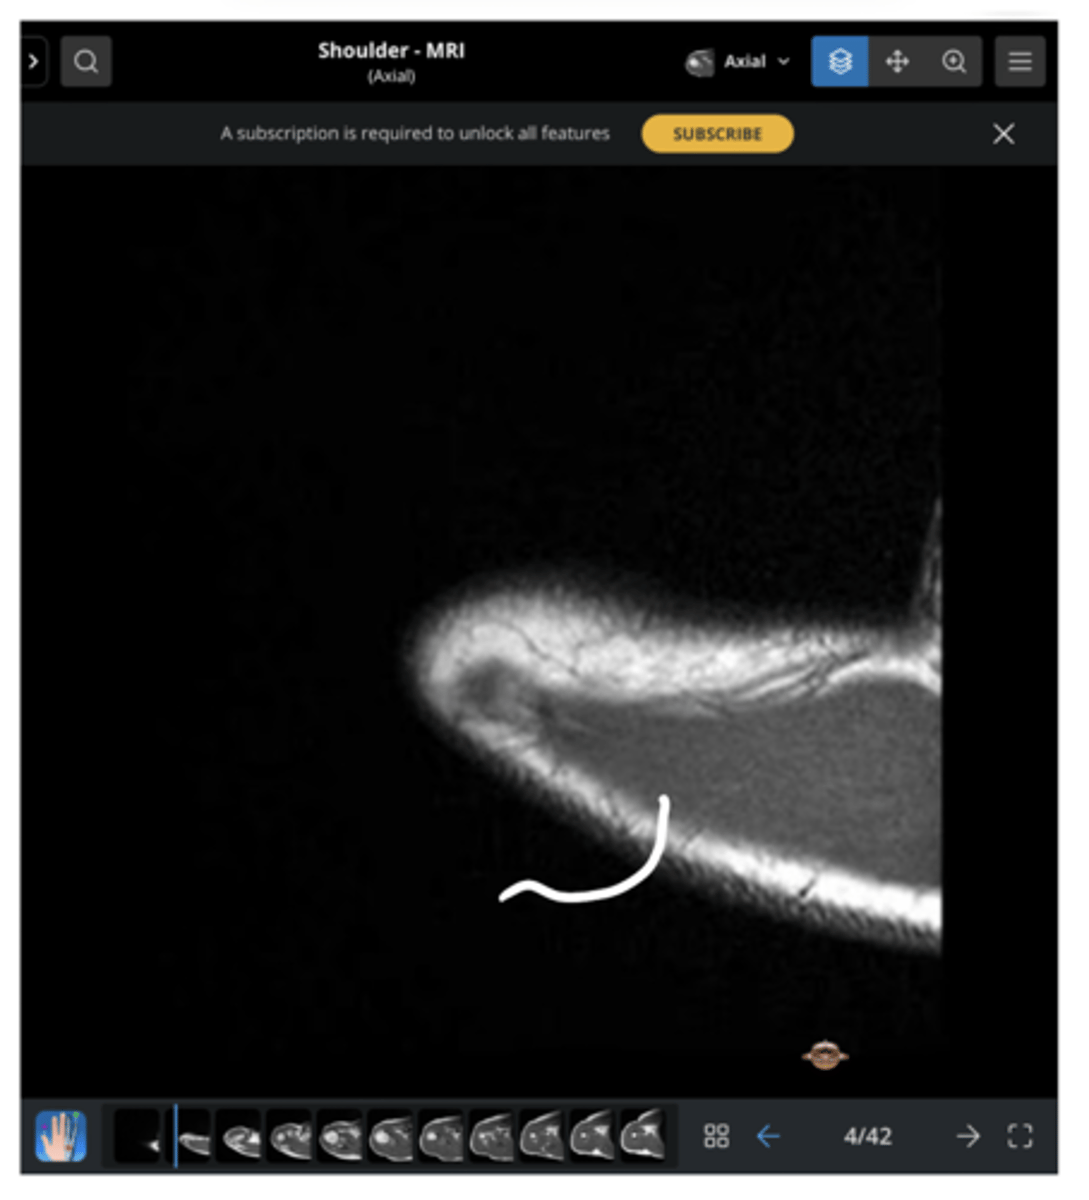

An axial view of the AC joint

What is this image depicting?